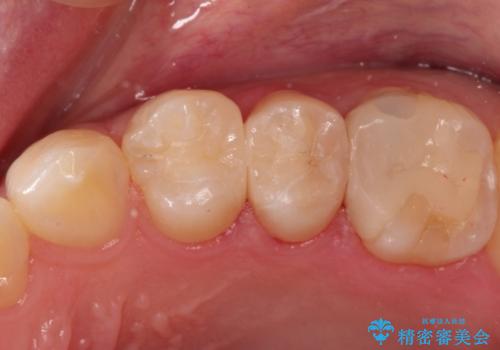

精密なむし歯の治療 セラミックインレー

- 定期健診にてむし歯を認めた患者さまです。

笑った時に見える部分だったためセラミックインレーにて修復しました。

保険治療で使える材料には制限があり、見た目だけでなく精度でも劣ります。当院でのセラミックインレーは歯とのつなぎ目を拡大鏡で確認して精度高く仕上げるため、むし歯のリスクを限りなく少なくできるよう治療します。